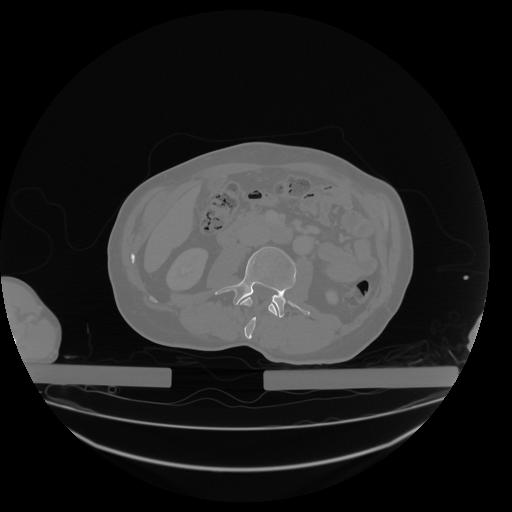

34 CUERPO,CE,Vol,1.0,CUERPO,,